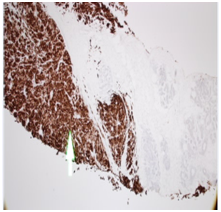

Staging CT chest & abdomen, showed bilateral lung nodules and numerous subcutaneous nodules, the largest seen in the umbilical area (Figure 4). Histology of the right breast biopsy reported staining for Melan-A & HMB45 is positive (Figures 5A‒5D). No staining for Cam5.2, ER, PR, CK7 and CK20. Ki67 is 10%. Appearances and immuno-profile are consistent with metastatic malignant melanoma. Due to disease dissemination, the patient has been referred to palliative oncological treatment.

Figure 5(C) x10 sheets of melanocytes positive for HMB45. Normal breast lobules at 12 o’clock do not stain for HMB45.

Figure 5(D) x40 sheets of melanocytes on the left are positive for Mel A. Normal breast lobules on the right do not stain for Mel A.